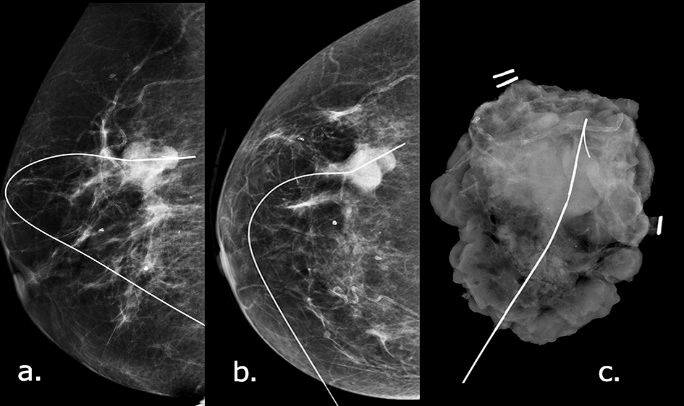

After MDM discussion, a wire-guided excision biopsy (Figure 5) was decided upon and performed. The excision contained a 21 mm well-circumscribed lesion composed of cystic spaces set in a sclerotic, hyalinised stroma. The cysts were lined by a mixture of squamous and mucinous epithelium with mild cytological atypia.

Figure 5: Wire localization mammograms (a) MLO, b) CC view) that show a Hawkin’s III wire going through the lesion in the upper outer quadrant of the right breast. The surgical specimen c) shows the lesion situated within the specimen.